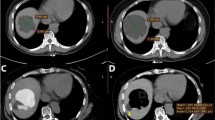

For group B, the puncture route was designed to avoid the renal parenchyma, and the needle tip was located near the cyst base. After injecting diluted contrast agent to confirm normal conditions, 3–5 mL of 2% lidocaine was injected into the cyst and retained for 1 min. Next, based on the estimated cyst volume, most of the fluid within the cyst was aspirated, with retention of only 10–20 mL. This enabled the operator to confirm that the needle tip was within the cyst by steadily aspirating 1–2 mL of fluid. Then, 99.9% ethanol (not more than 200 mL) was injected into the cyst to occupy approximately 75% of the original volume, which was calculated based on the estimated cyst volume. This aspiration and injection cycle with the same volume was repeated. Typically, following completion of the second or third replacement, the ethanol concentration in the cyst cavity exceeded 90% and remained unchanged for 5 min under the same patient position (Figs. 1, 2). Ethanol was then withdrawn, followed by the same procedures performed for patients in group A.

A 74-year-old female with persistent pain in the right loin for 2 months. (A) The cyst was not punctured through renal parenchyma considering that the needle tip was located at the cyst base. (B) During replacement, at least 10–20 mL of liquid was retained in the cyst for the operator to confirm that the needle tip was inside the cyst. At this point, even though the cyst wall collapses, the needle tip near the cyst base remains within the cyst. (C) After completing the second replacement, approximately 75% of the cyst volume of the ethanol was retained in the cyst, with a CT value of −214 HU, indicating an ethanol concentration of >90%, which was retained for 5 min. (D) After the procedure, the cyst wall completely collapsed and the cyst cavity disappeared.